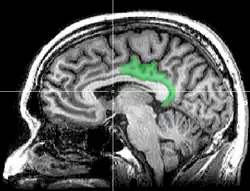

Sagittal MRI slice with highlighting indicating location of the posterior cingulate | |